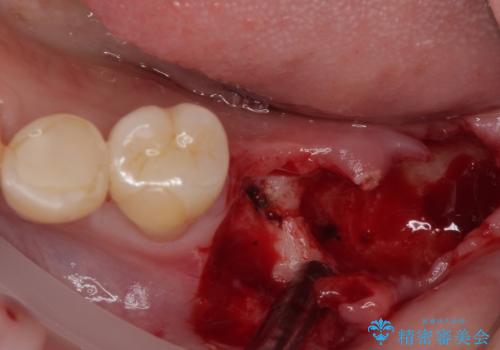

- ブリッジの土台から膿が出るとのことで来院された患者様です。

不均衡で無理な力がかかってしまうブリッジを装着したため、最後臼歯周辺の歯槽骨が溶けている状態でした。

上顎は最後臼歯が欠損しているため、ブリッジの土台は抜歯し、元々の欠損部にインプラントによる補綴治療を行うこととしました。

支台歯の骨欠損は予想以上に大きく、即時荷重インプラント部への影響が心配されましたが、無事に最短期間で治療を終えることができました。